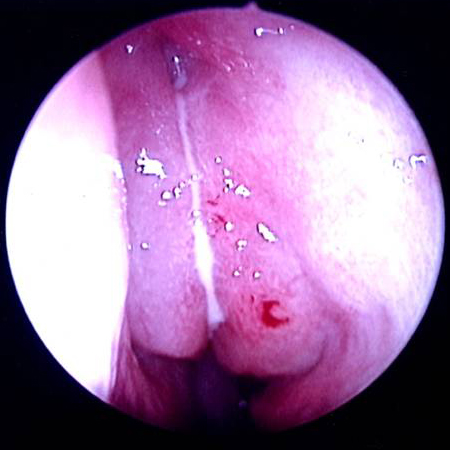

აუცილებელია ცხვირის ღრუს შემოწმება ლორწოვანი გარსის ერითემის ან ჩირქოვანი გამონადენის არსებობაზე. ოპტიმალური შემოწმების ჩატარება შესაძლებელია შეშუპების საწინააღმდეგო სპრეის ლოკალური დატანების შემდეგ.[17] როგორც ოტოსკოპი, ისე ნაზალური სარკე და რეფლექტორული განათება შეიძლება იყოს გამოყენებული. ცალმხრივი ჩირქოვანი გამონადენი, ლორწოვანი გარსის შეშუპება ან ერითემა, აგრეთვე სახის არეში მტკივნეულობა მიანიშნებს ბაქტერიული სინუსიტის არსებობაზე. არაჩირქოვანი გამონადენი საფიქრებელს ხდის ვირუსული ან ალერგიული ანთების არსებობას. იმის გათვალისწინებით, რომ ნაზალური გასინჯვა შესაძლოა იყოს გაძნელებული, ან ავლენდეს მხოლოდ არა-სპეციფიურ ნიშნებს, ცალკეული პაციენტებისთვის რეკომენდებულია ნაზალური ენდოსკოპიის ჩატარება, კერძოდ, ემპირიული ანტიბიოტიკოთერაპიის მიმართ რეფრაქტერული პაციენტებისთვის, როდესაც არსებობს ეჭვი ანტიბიოტიკებისადმი რეზისტენტობაზე, ან პაციენტი არის იმუნოკომპრომენტირებული.

ენდოსკოპია იძლევა ცხვირის ღრუს და სინუსების სადრენაჟე გზების საუკეთესო ვიზუალიზაციის საშუალებას. არსებობს ორი ტიპის ენდოსკოპი: რიგიდული და ელასტიური. რიგიდულ ნაზალურ ენდოსკოპს უკეთესი რეზოლუცია გააჩნია და მისი მართვა ცალი ხელით შეიძლება. ეს აადვილებს საჭიროების შემთხვევაში კულტურების მიღებას ცხვირის ღრუდან ან წიაღიდან. ელასტიური ნაზალური ენდოსკოპი პაციენტებისთვის უფრო კომფორტულია, მაგრამ მისი მართვა ორივე ხელის დახმარებით ხდება. არსებობს დრეკადი ცხვირის ენდოსკოპი, რომელსაც აქვს კულტურის შეგროვების არხი, მაგრამ უფრო დიდი და არასასიამოვნოა და მათი დამუშავებაც უფრო რთულია. ზოგადად, დრეკადი ენდოსკოპის გამოყენება უმჯობესია ბავშვთა ასაკში მისი კარგი ამტანობის გამო; თუმცა როგორც მოზრდილების, ისე ბავშვთა გამოსაკვლევად შესაძლებელია ორივე ტიპის ენდოსკოპის გამოყენება. არჩევანი დამოკიდებულია შემსრულებლიექიმის გამოცდილებაზე და შემთხვევათა უმეტესობაში იშეიძლება ჩაატაროს ყელ-ყურ-ცხვირის სპეციალისტმა.

[Figure caption and citation for the preceding image starts]: მარცხენა შუა გასასვლელი ძლიერი შეშუპებით და ჩირქოვანი სეკრეტებითექ. Melissa Pynnonen-ის კოლექციიდან [Citation ends].